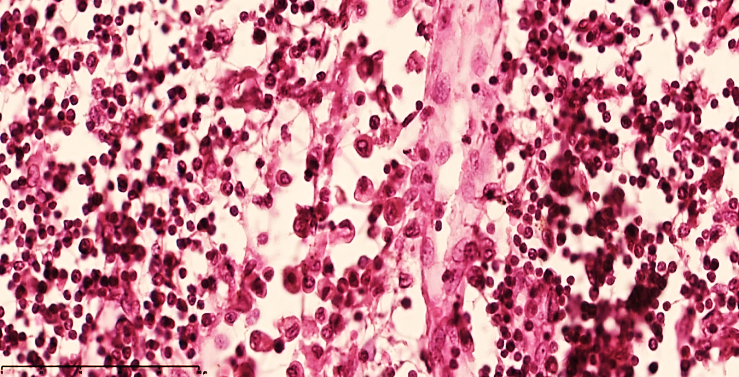

| Figure 3. Mesenteric lymph node of a 28-day-old infant with peritonitis. Macrophages are increased in the peritrabecular area, lymphocytes are decreased, and oligonucleated lymphoblasts are increased, and stroma is disrupted. Staining G.E. Size 40x10 |

Lymphostasis and dilatation of lymphatic capillaries are preserved in the lymph nodes. In the subcapsular area of the lymph node, a small number of macrophages and lymphocytes are detected in the spaces where the cyst has expanded. Areas of regenerating V-lymphocytes in the cortical area are defined, although the lymphoid follicular boundaries and texture are uneven (see Fig. 4). | Figure 4. Mesenteric lymph node of a 28-day-old infant with peritonitis. Treated on the 6th day. Macrophages increased in the peritrabecular area, lymphocytes and plasma cells decreased, and oligonucleated lymphoblasts increased, and stroma was found to be disrupted. Vascular dilation and collapse were detected. Staining G.E. Size 40x10 |